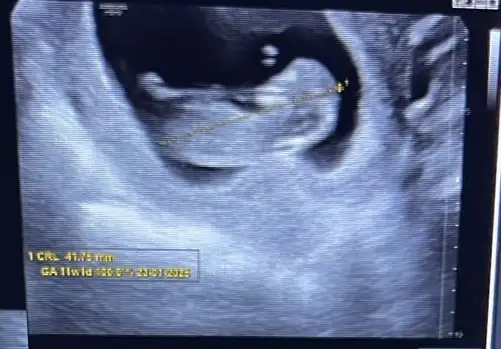

13.haftamızdayız cinsiyet tahminlerinizi yazar mısınız :)🌸

Doktor %70 kız olabilir ama net değil dedi. Benimde hep içimde kız vardı taaaki bu ultrasona kadar. Nedensebu ultrasonda erkek hissettim. ☺

Lütfen haber edin. Merak ettim. Net olmasa da erkek gibi bayağı